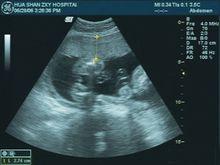

臨床超聲影像學醫學超聲影像學是臨床醫學、聲學和電子計算機科學之間的交叉學科。近年來,隨著聲學理論和電子計算機科學的迅速發展,醫學超聲影像學的新技術層出不窮,諸如三維超聲成像、諧波成像、超聲像生物顯微鏡、血管內超聲等,大大地拓展了超聲影像學的臨床套用範圍。毋庸質疑,醫學超聲影像學已成為臨床醫學中不可缺少的、自成體系的一門獨立學科,極大地豐富了臨床醫學的內容,拓展了臨床醫學的領域,為醫療衛生事業的發展做出了積極的貢獻。為及時反映超聲影像學領域內基礎理論和臨床套用方面的最新成就,促進臨床超聲影像學的深入研究和普及推廣,我們受人民衛生出版社的委託組織了國內外近百名理、工、醫各方面的知名專家共同編撰了這部大型專業參考書。

全書共10篇120章,第一篇介紹醫學超成像原理及有關儀器設備,第二篇重點介紹心臟與大血管疾病的超聲檢查及診斷要點,第三篇至第十篇描述除心血管外的各器官組織疾病。讀者對象:超聲科醫師及專業人員。